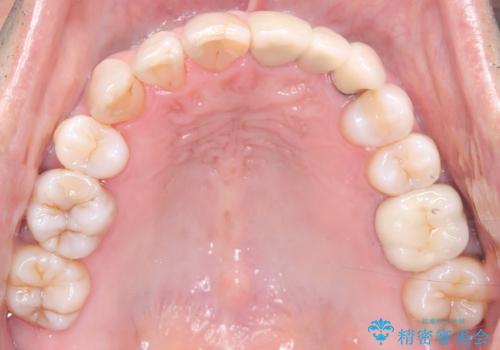

- 50代の患者様で、右上の八重歯と歯並びの乱れを気にされてご来院されました。特に、すでに装着されている前歯のセラミックブリッジを外したくないという強いご希望がありました。精密な検査の結果、八重歯を治すためのスペースが不足しているため、右上の4番目の歯(小臼歯)を抜歯し、そのスペースを利用して歯並び全体を整える治療計画を立案。装置には目立たないインビザラインを採用し、ブリッジを温存しながら八重歯の改善を目指しました。

今回の治療で最も重要だったのは、患者様のご要望通り既存のセラミックブリッジを外さずに矯正を進める点でした。計画通り右上の小臼歯を抜歯し、透明なインビザラインを使用して抜歯スペースを閉じながら、八重歯を正しい位置へ移動させました。ブリッジの形態と調和するに、他の歯の移動を工夫をすることで、複雑な条件をクリア。治療の結果、長年気にされていた八重歯が解消され、見た目が大きく改善しました。50代からでも、ご自身の要望を叶えながら、美しく機能的な歯並びを獲得していただけました。